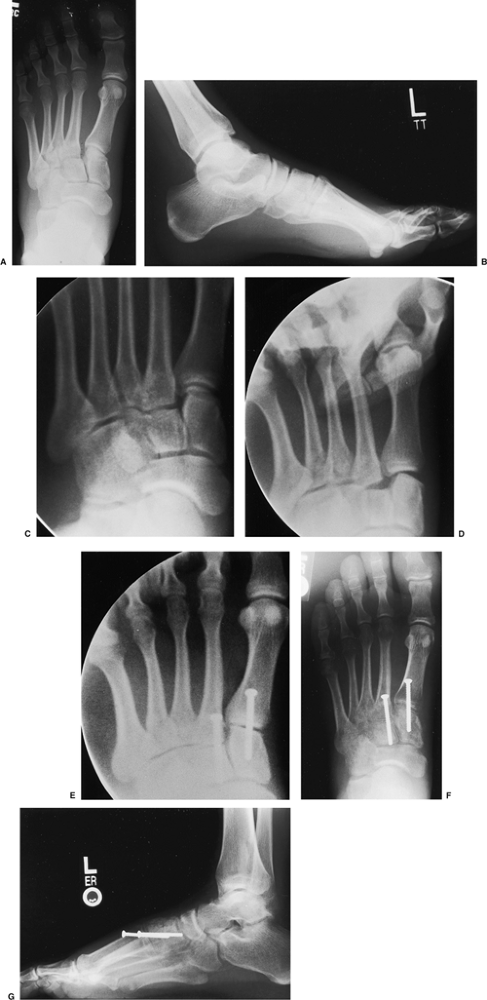

Figure 36.2. A. An AP x-ray demonstrating a subtle Lisfranc injury. The base of the second metatarsal is displaced laterally. B.

This lateral x-ray, taken under nonweight-bearing conditions, shows that the dorsal cortex of the second metatarsal is subluxed dorsally relative to its cuneiform. C. A scout view is used to confirm that the foot is in the correct position for assessing the tarsometatarsal joints. D. The stress x-ray reveals instability in the first, second, and probably third tarsometatarsal joints. E. An intraoperative fluoroscopic image taken after fixation reveals that the third metatarsal is stable. F. Six weeks following surgery, the reduction appears anatomic and the clinical position of the foot is good. G. Alignment of the metatarsal bases is restored in both planes. |